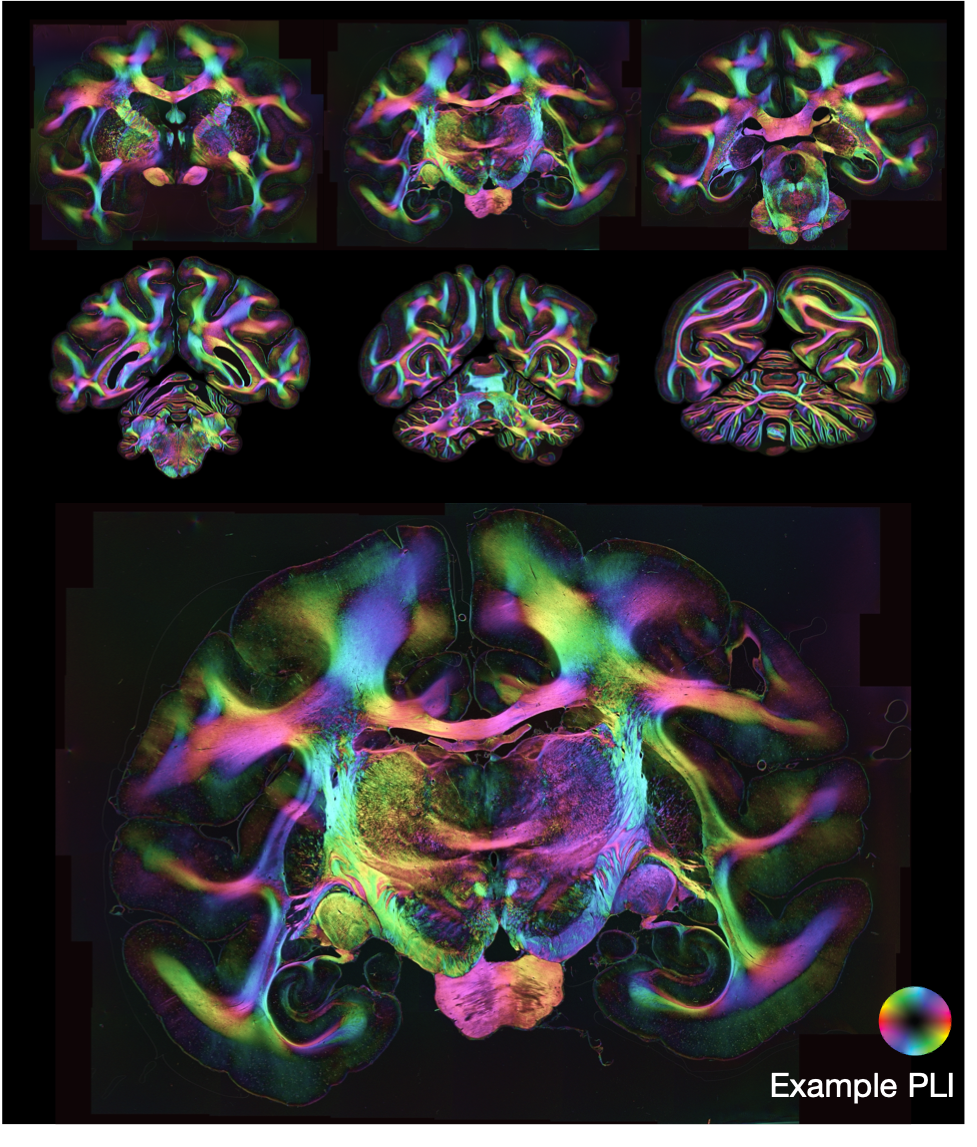

Polarised light imaging

Polarised light imaging (PLI, Axer2011) utilises the birefringence of myelin to estimate the primary fibre orientation per microscopy pixel. The BigMac dataset includes 2D PLI at a resolution of ~ 4μm/pixel, where we infer maps of the transmittance, retardance and orientation of axons within the 2D microscopy plane (see definitions below).

To aid interpretation, a composite hue-saturation-value (HSV) image is generated where the hue is defined by the in-plane angle and the value given by the retardance.